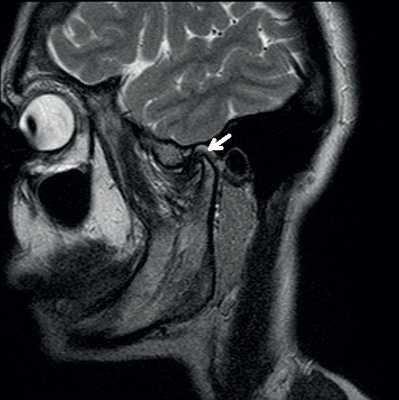

Косо-сагиттальная проекция с закрытым ртом. Нормальный ВНЧС.

Суставной диск не дислоцирован, задняя его часть находится на 12 часах циферблата мыщелка.

Нормальная мобильность диска

Позиция с открытым ртом. Мыщелок сместился вентрально, на уровень суставной ямки. При этом суставной диск сохранил нормальное положение интерпозиции, не давая костным структурам напрямую контактировать друг с другом.